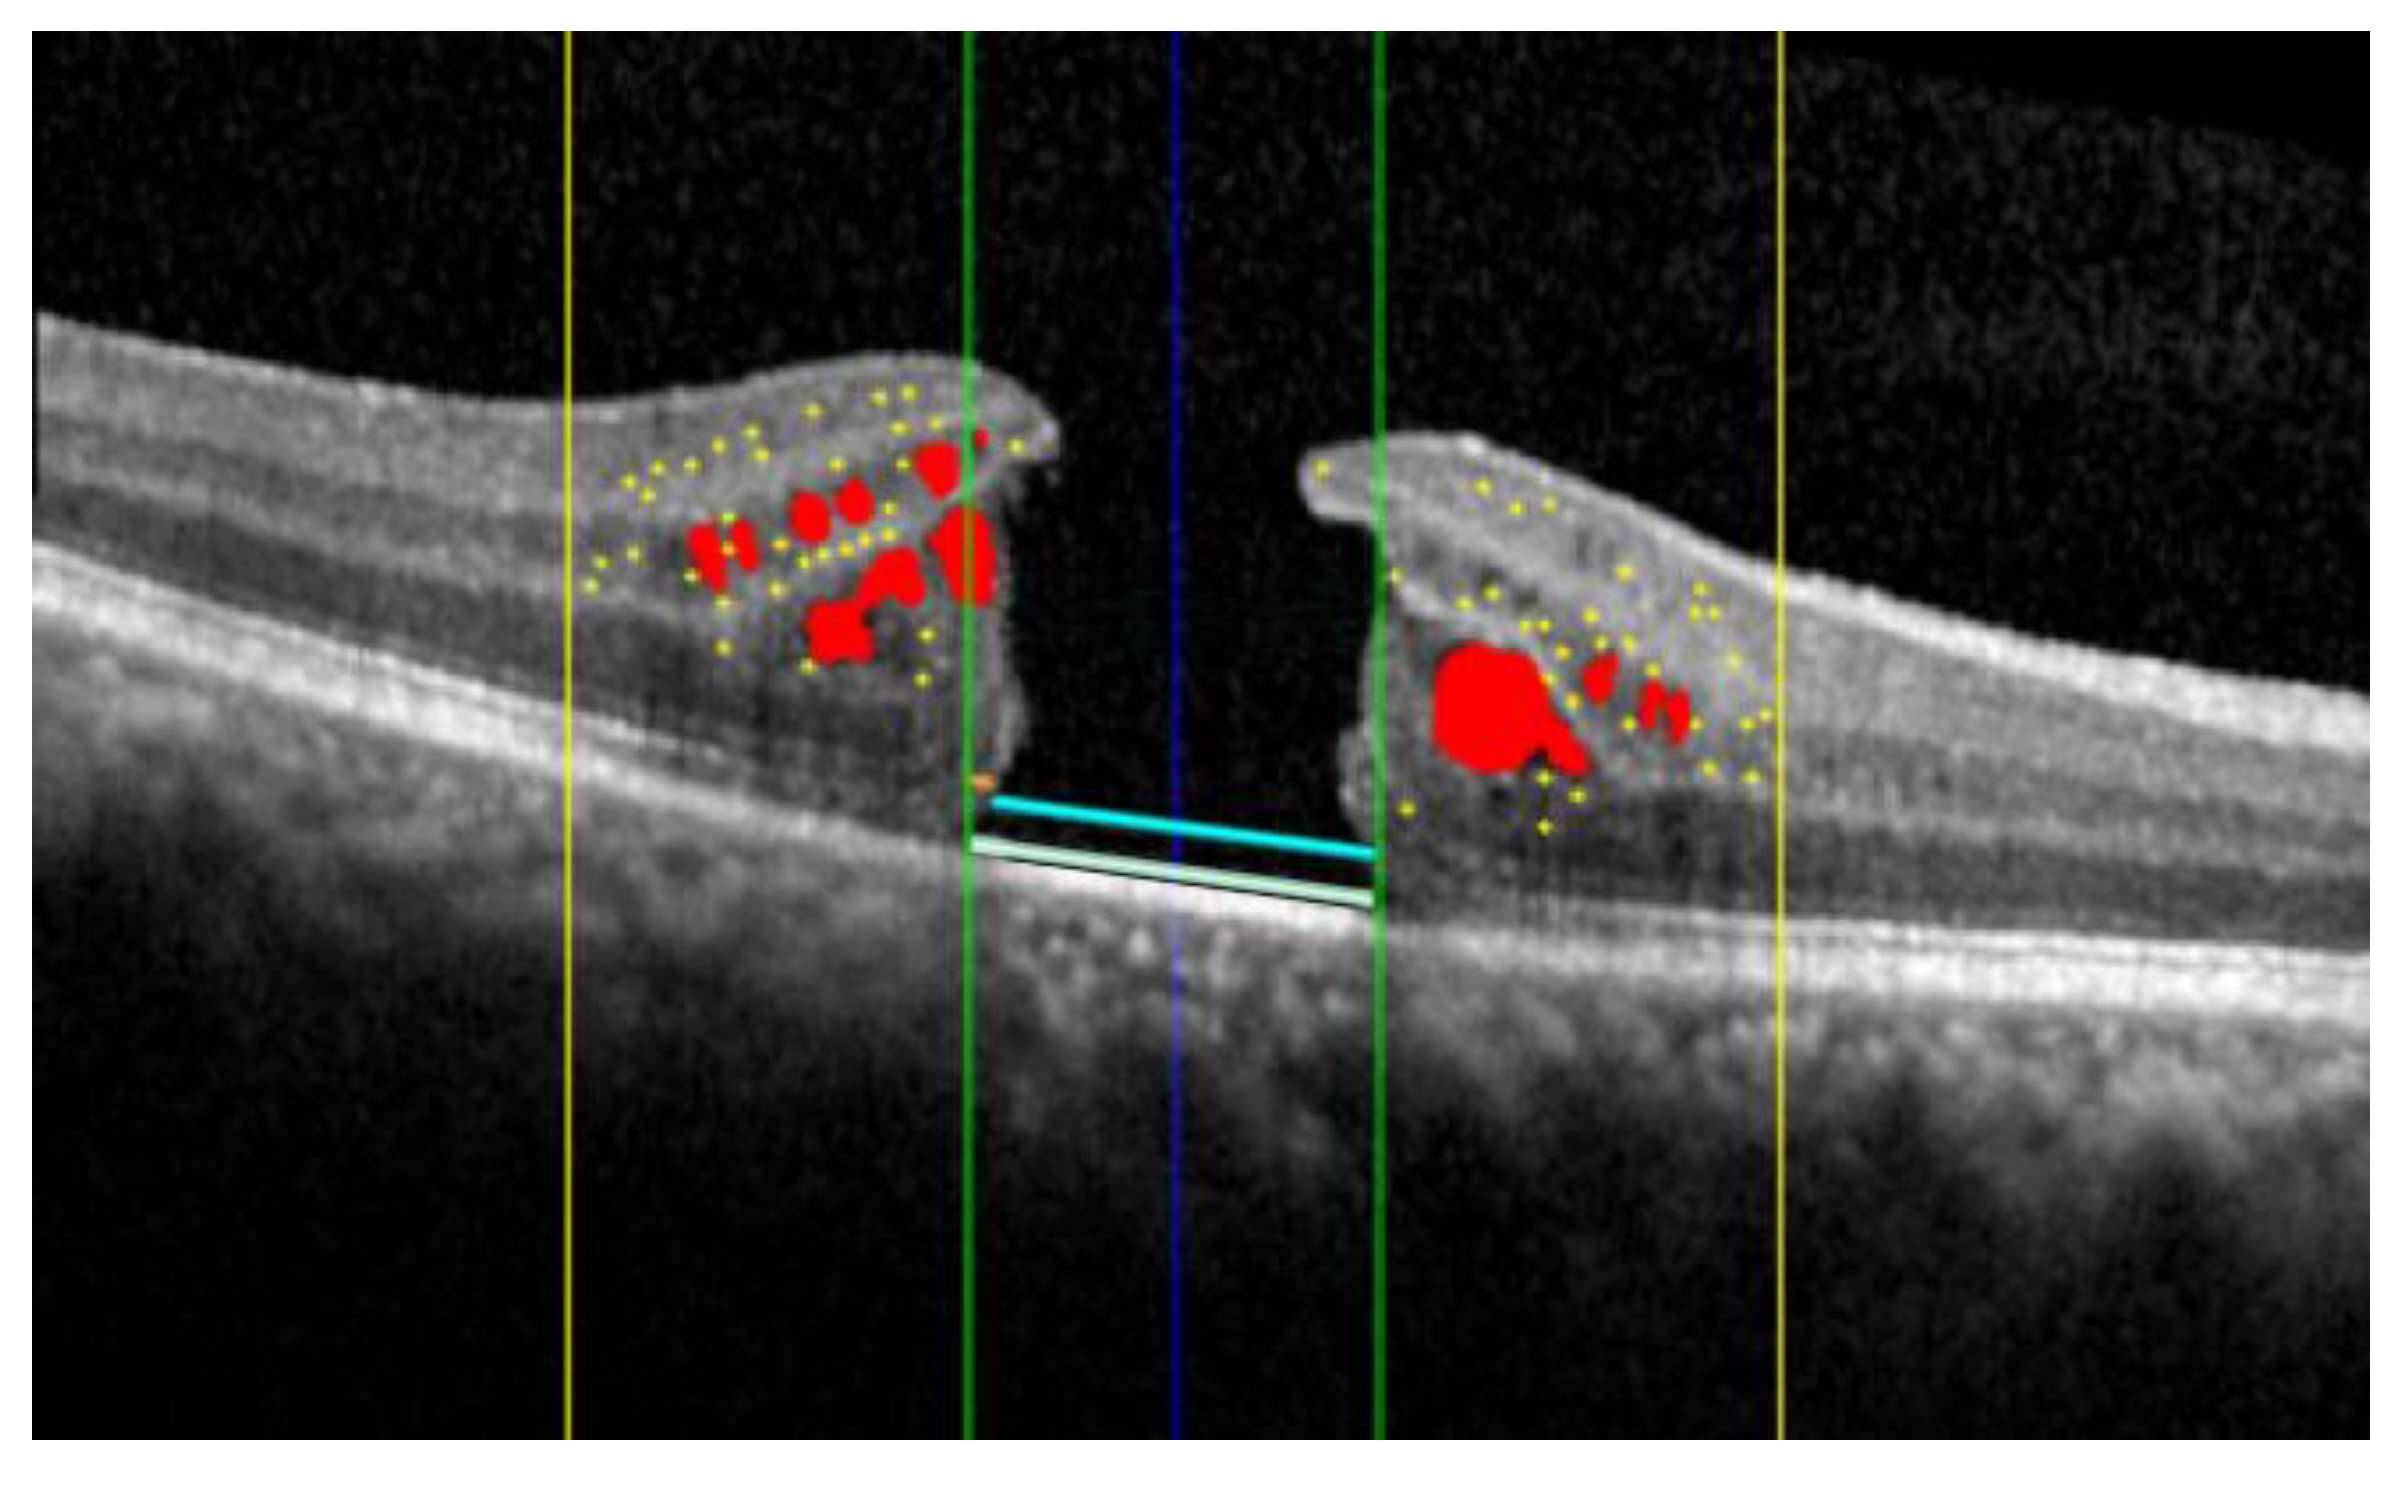

The AI algorithm allows for the simultaneous evaluation of several OCT biomarkers, as illustrated in Figure 1 and Figure 2.

Figure 2.

Summary of another case. The baseline OCT (A) and the postoperative OCT (B) are shown. The AI assessments of the biomarkers were overlaid (C): HRF (yellow dots) localized within the central 3 mm (yellow lines); ELM (orange) and EZ (yellow) localized within the central 1 mm (green lines); SRF (blue).